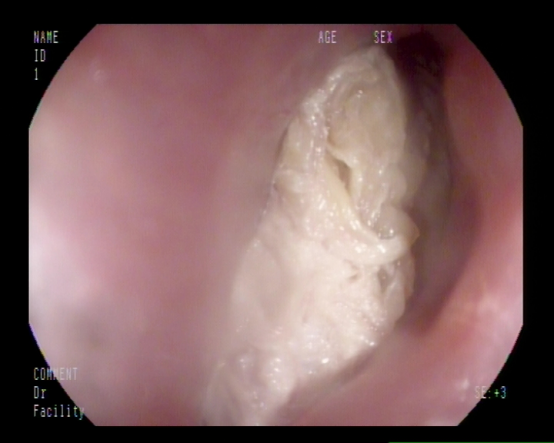

麻醉完成后,胃镜下可见食道上端入口处横卧着团块状食物堵住了整个食管入口,初步判断为鸡肉,距离门齿仅15cm。梁政主治医师在胃镜下通过活检钳、爪钳、圈套器试图把食物取出,初步判断为鸡肉。但因鸡肉块状已局部消化,难以整块取出,稍有不慎容易刺破食管或滑入气管,后果不堪设想,情况十分危急。